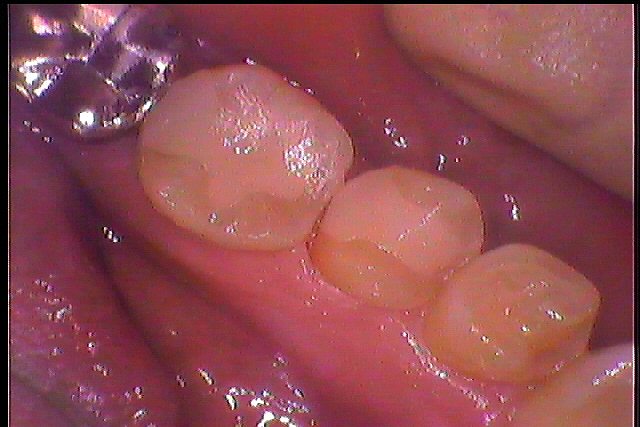

左下2本虫歯治療からのセラミック治療へ|お知らせ |広島市安佐南区の歯科医院 左下2本虫歯治療からのセラミック治療へ トップ お知らせ・ブログ お知らせ 左下2本虫歯治療からのセラミック治療へ 左下2本虫歯治療からのセラミック治療へ このような銀歯が入っていました 銀歯を外したところになります このように虫歯が存在します 左下5番も虫歯があります 頬側部にも下に虫歯が、、、 除去しCRにて覆罩しました セレックセラミックシステムにてセラミックを作成し、覆罩しています このようにきれいに入りました 見えるところなので気にされていました Web診療予約 初めての方へ 選ばれ続ける理由 院内設備について 歯が痛いしみる一般歯科 歯がぐらぐらする歯周病 健康な歯を保ちたい予防歯科 子供の虫歯予防をしたい小児歯科 銀歯をセラミックに審美歯科 白い歯を目指しませんか?ホワイトニング 矯正専門医がいるので安心矯正歯科 抜けた歯を補いたいインプラント・入れ歯 医院案内 スタッフ紹介 メリィハウス歯科クリニックオフィシャルホームページ ラベンダー歯科クリニックオフィシャルホームページ お知らせ・ブログ ホーム 診療科目 一般歯科 歯周病治療 予防治療 小児歯科 審美治療 ホワイトニング 矯正歯科 入れ歯・インプラント マウスピース矯正 初めての方へ 院長・スタッフ 設備紹介 医院案内・アクセス メニューを閉じる